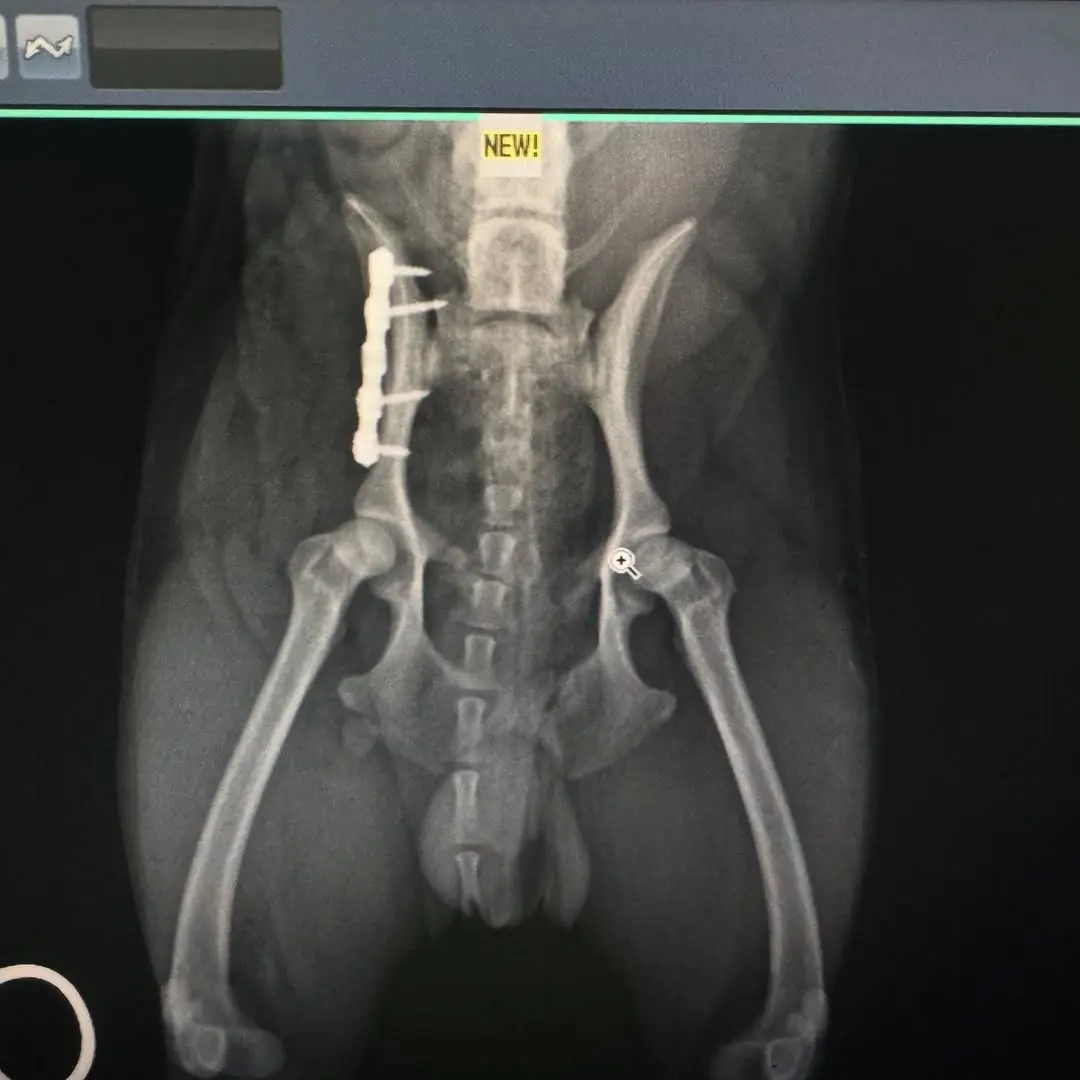

Kırık Ameliyatları: Kemik kırıkları, plak, vida ve tel sistemleri kullanılarak onarılır.

Pelvis ve Kalça Kırıkları: Parçalı pelvis kırıkları ve kalça çıkıkları, özel tekniklerle tedavi edilir.

Görüntüleme ve Tanı: Röntgen, ultrason gibi görüntüleme yöntemleriyle tanı konulur.

Cerrahi Müdahale: Gerekli görülürse, cerrahi müdahale gerçekleştirilir.